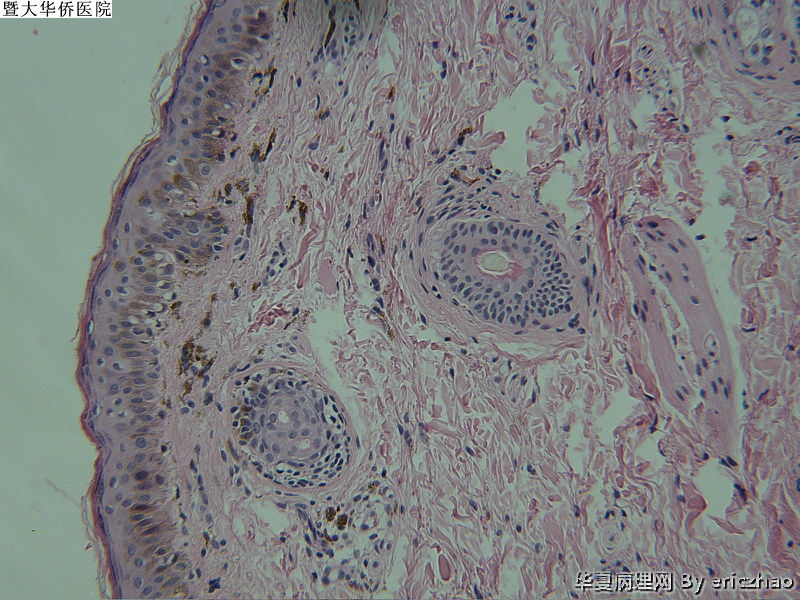

29岁女性的颞侧黑斑片的诊断

病史2年,斑片缓慢扩大,活检部位为斑片中央,临床怀疑是色素痣

参考诊断

交界痣?早期SK?